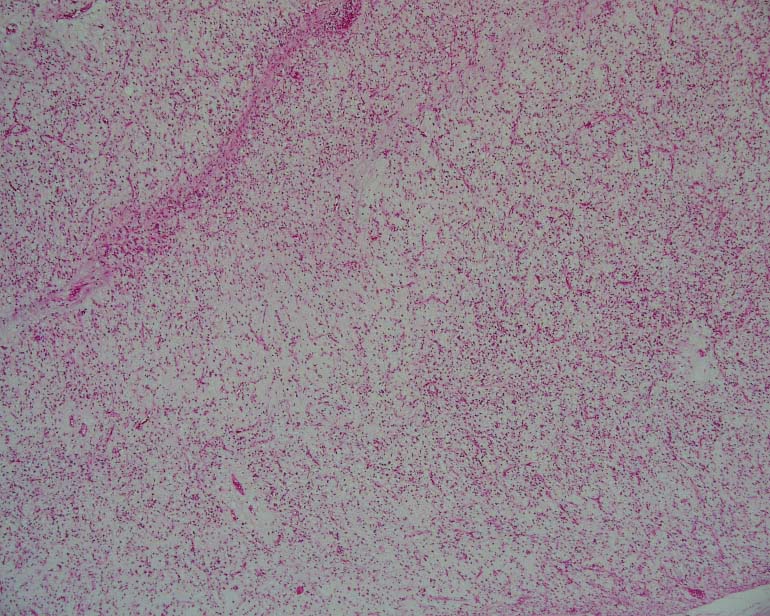

粘液型脂肪肉腫(myxoid liposarcoma)は高分化型に次いで多く見られる脂肪肉腫で、粘液性の基質を背景として、腫瘍細胞であるリング状の脂肪芽細胞と、円形から卵形の核を持った非脂肪性の間葉細胞が増殖したものである。粘液型脂肪肉腫の多くに、t(12;16)(q13;p11)の相互転座を認め、この転座により生じるTLS-CHOPキメラ遺伝子は診断の補助に用いられる。壊死を伴うないし円形の核を持った細胞が多く存在するといったものは悪性度が高く予後は悪い。粘液性脂肪肉腫は他の型の脂肪肉腫に比べると、放射線感受性が高い。